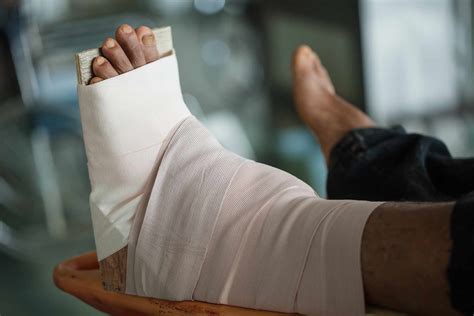

• Immediate Post-Operative Care: After surgery, you will be monitored in the recovery room. Pain management will be a priority, and you may be given medications to control discomfort. You will also be instructed on how to care for your incision and manage swelling.

• Non-Weight-Bearing Period: For the first few weeks, you will need to keep weight off your ankle to allow the bones to heal properly. This may involve using crutches, a walker, or a wheelchair.